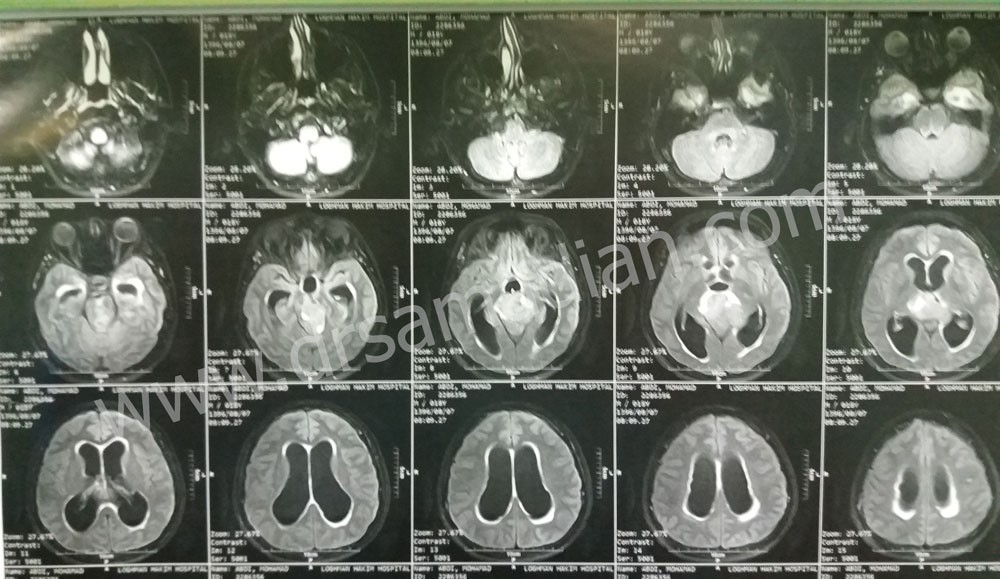

تصاویر زیر مربوط به بیمار آقای ۱۹ ساله است که با شکایت سردرد و عدم تعادل مراجعه کرده است. از حدود یک سال قبل دچار سر درد بوده است. سر درد درتمام سر منتشر شده و فشاری است . از یک هفته قبل از جراحی دچار عدم تعادل شده و یک ماه قبل دچار کاهش شنوایی شده است. هم چنین دو ماه پیش دچار تاری دید شده است . همانطور که مشاهده می کنید تومور آن توسط دکتر صمدیان خارج شده است :